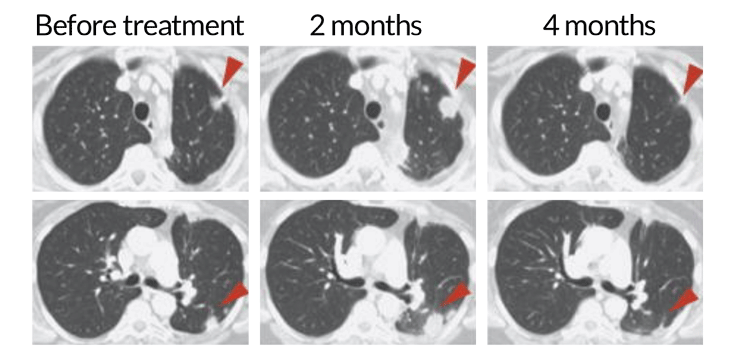

A patient with non-small cell lung cancer received a treatment targeting the T cell protein PD-1, unleashing the cells to fight the cancer. At two months, the T cells have infiltrated the tumor (red arrows), making it appear bigger. But at four months, the immune cells’ continued attack has shrunk the tumor.